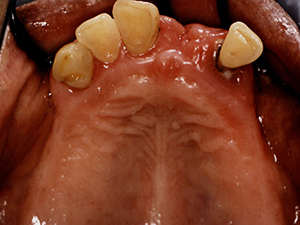

【治療前】

【装着前】